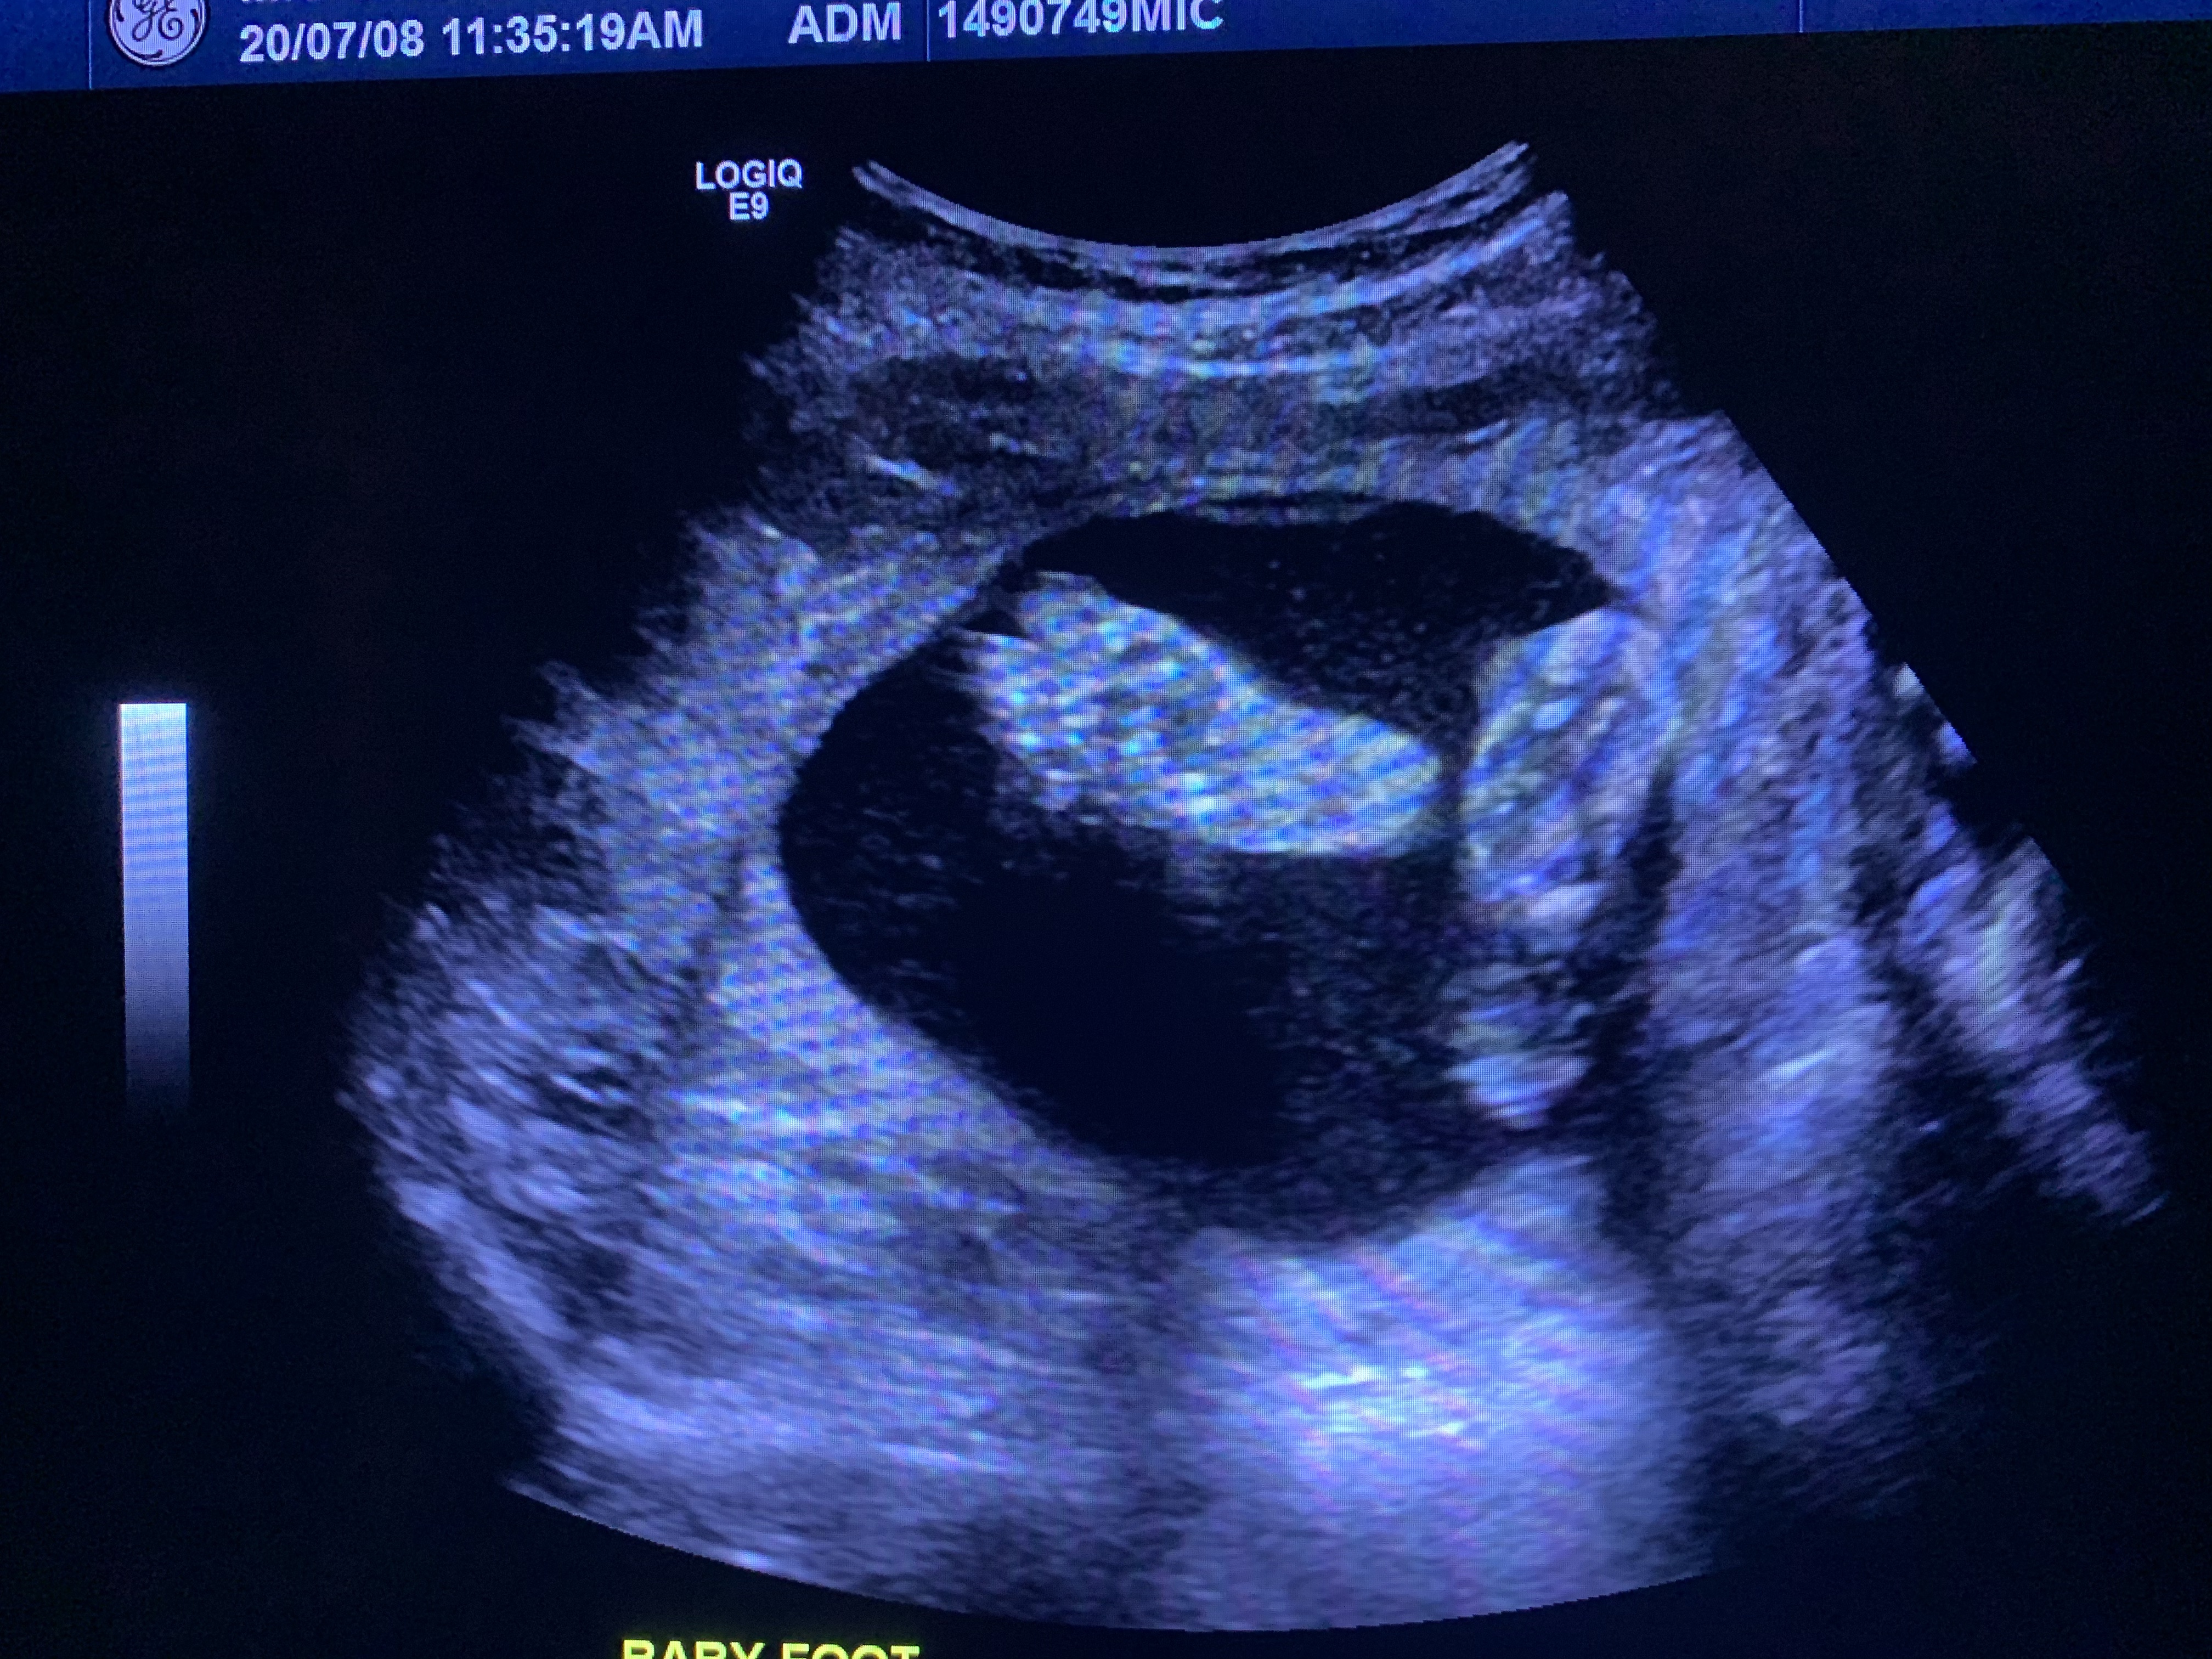

7 ultrasounds

He has always remained healthy, growing and always has a very strong heartbeat. Oh yea and also the kicks, lets not forget the kicks 🙂